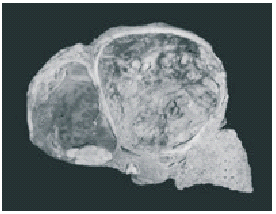

El hígado estaba aumentado de peso y tamaño, con aspecto cirrótico. En el lóbulo izquierdo se observó una lesión neoplásica, ovoidea, de 10 × 7 × 6,5 cm, de bordes bien definidos, color verde amarillento con áreas de color café, de consistencia blanda (Fig. 4). Los ganglios linfáticos del hilio hepático, peripancreáticos y mesentéricos presentaban aspecto metastático. Microscópicamente se observó una neoplasia epitelial maligna, con varios patrones: pseudoglandular (Fig. 5) sólido y en cordones. Las células neoplásicas eran grandes, con pérdida de la relación núcleo-citoplasma, pleomorfismo nuclear, nucléolo evidente y abundantes mitosis. En el resto del hígado, además de cirrosis inactiva, había múltiples nódulos de células neoplásicas en las que focalmente se identificó angioinvasión así como extensas áreas de necrosis. Las reacciones de inmunohistoquímica fueron positivas para Hepat y antígeno carcinoembrionario y negativas para a fetoproteína (Fig. 6). Con el conjunto de datos macroscópicos, microscópicos y de inmunohistoquímica se emitieron los siguientes diagnósticos: hepatocarcinoma bien diferenciado multicéntrico con patrón trabecular, acinar y sólido, asociado a cirrosis hepática de nódulos mixtos inactiva, con trombosis tumoral en venas hepáticas y metástasis en ganglios linfáticos peripancreáticos, del hilio hepático y mesentéricos; y mixoma auricular izquierdo con elementos glandulares.

Fig. 4. Hígado cirrótico y con el lóbulo derecho casi totalmente substituido por la lesión neoplásica.